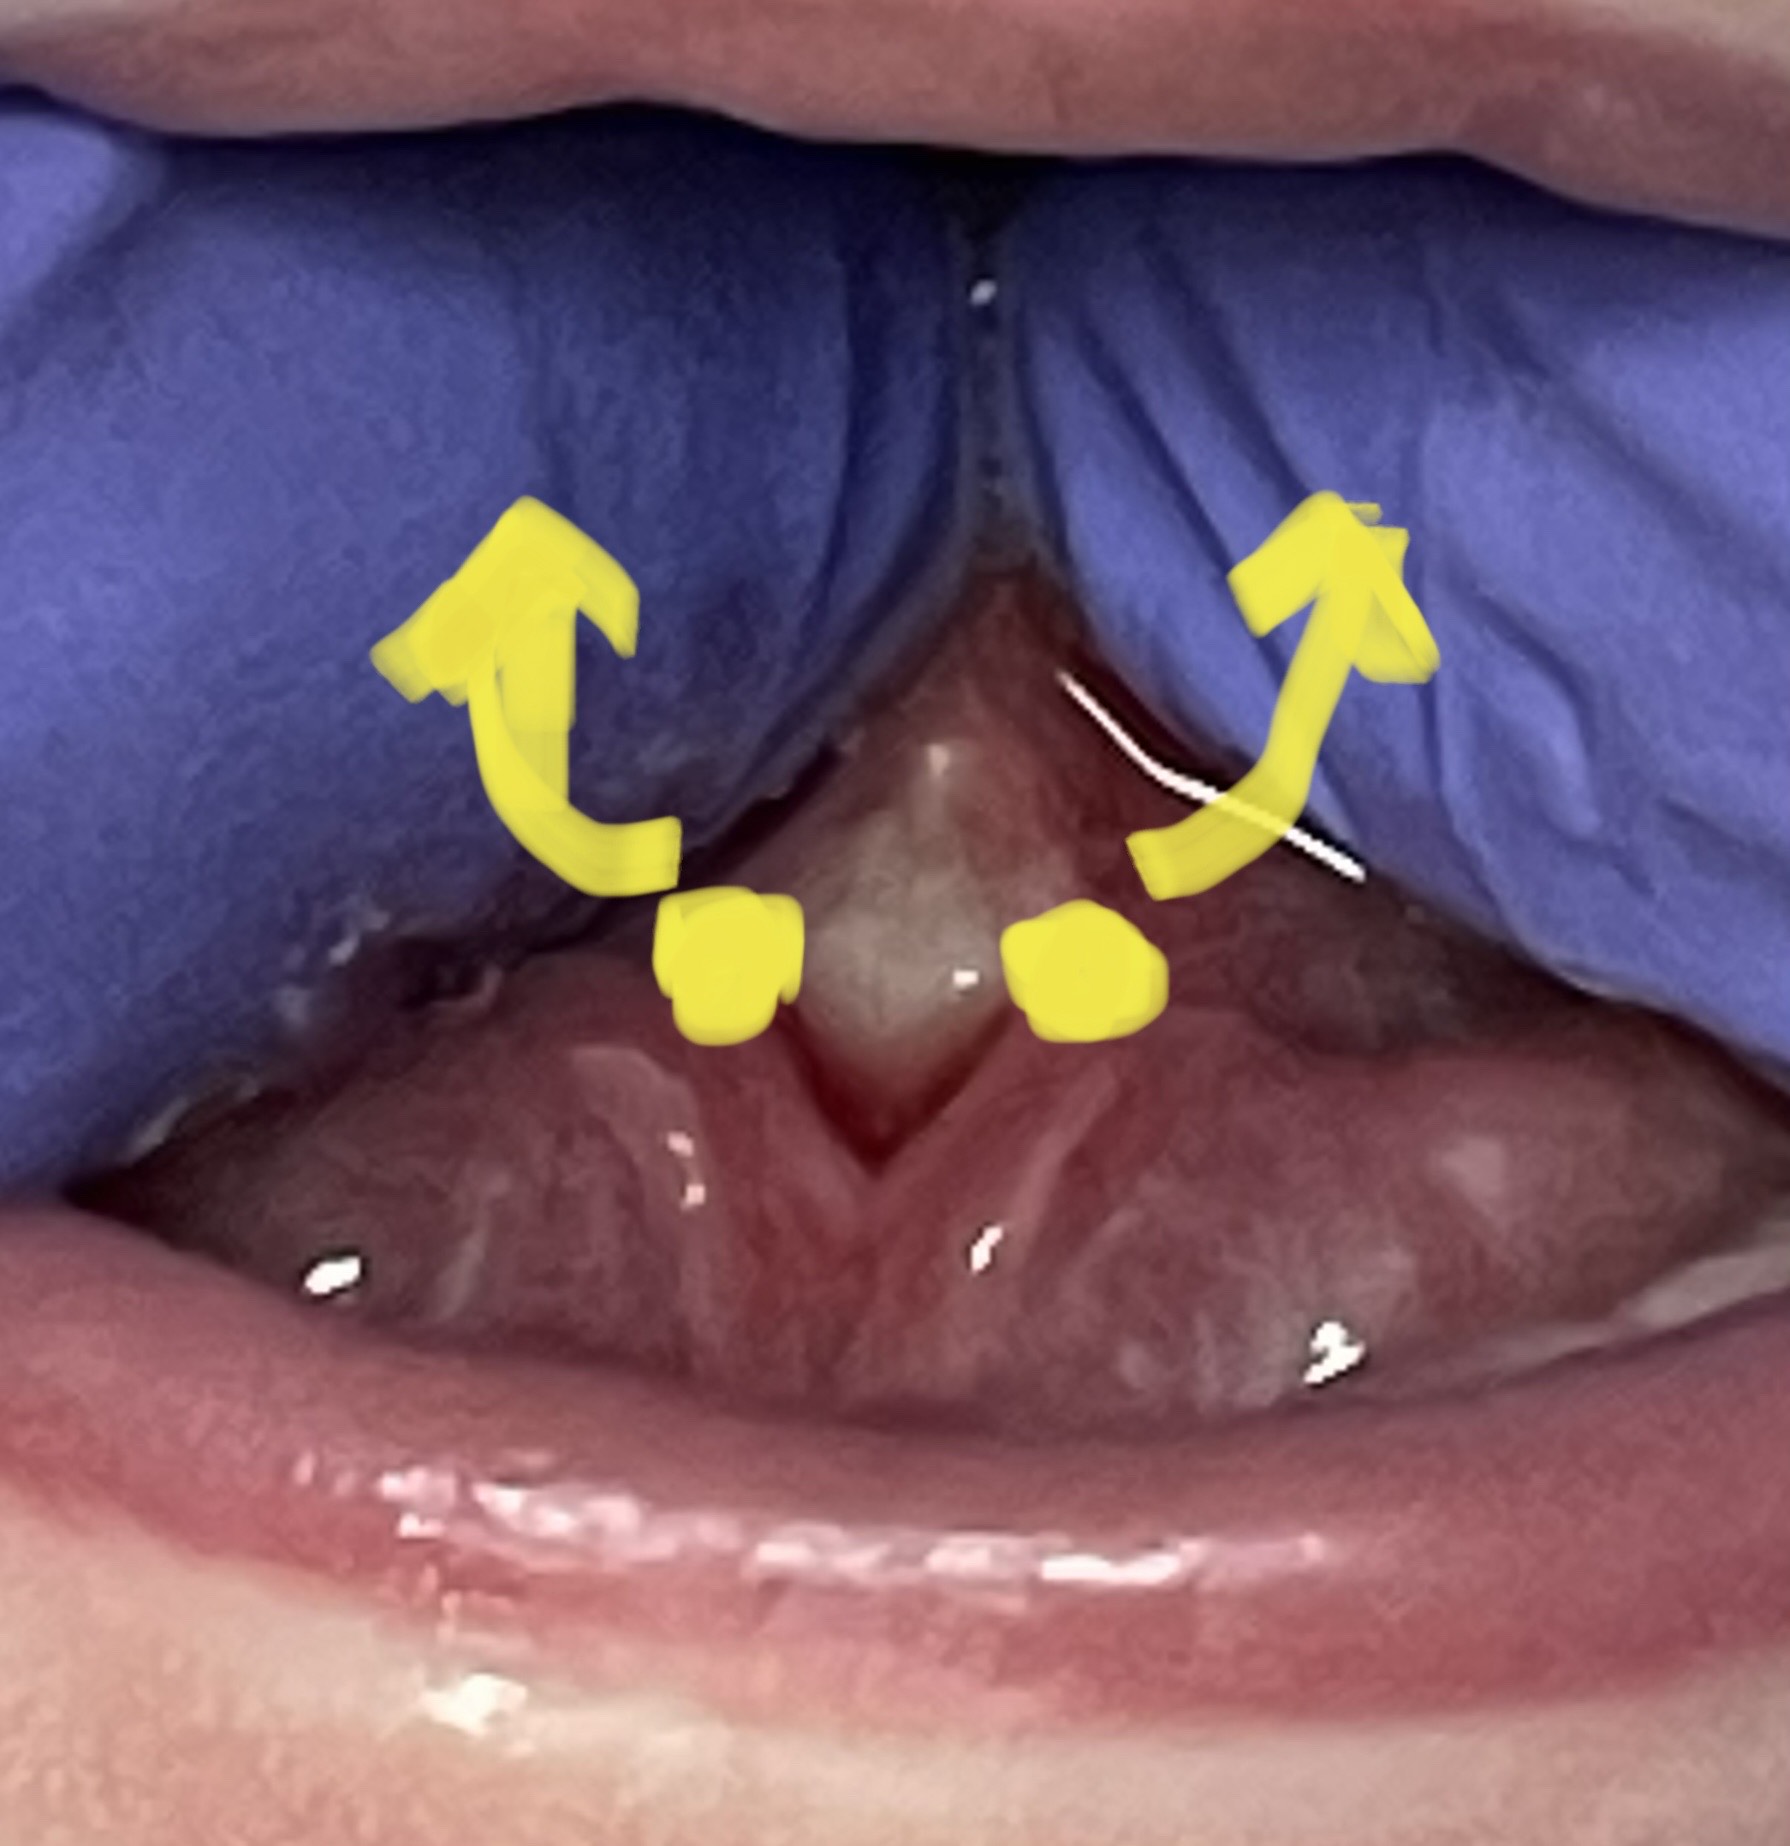

Tongue-Tie Release

Your goal is to have the frenum heal and re-form as far back as possible.

With a clean or gloved middle finger, STABILIZE the lower jaw by putting gentle pressure where the lower jaw and lip meet (baby will open when you do this). Use your pointer fingers to lift the tongue at the diamond in the middle of the tongue. Push your pointer fingers up and back, lifting the tongue. Your goal is to see the whole diamond open up and lengthen. Hold for five seconds.

It may bleed slightly when it is stretched, especially if there are longer times between stretches. If you see this, add slightly more pressure, or add one more stretch per day.